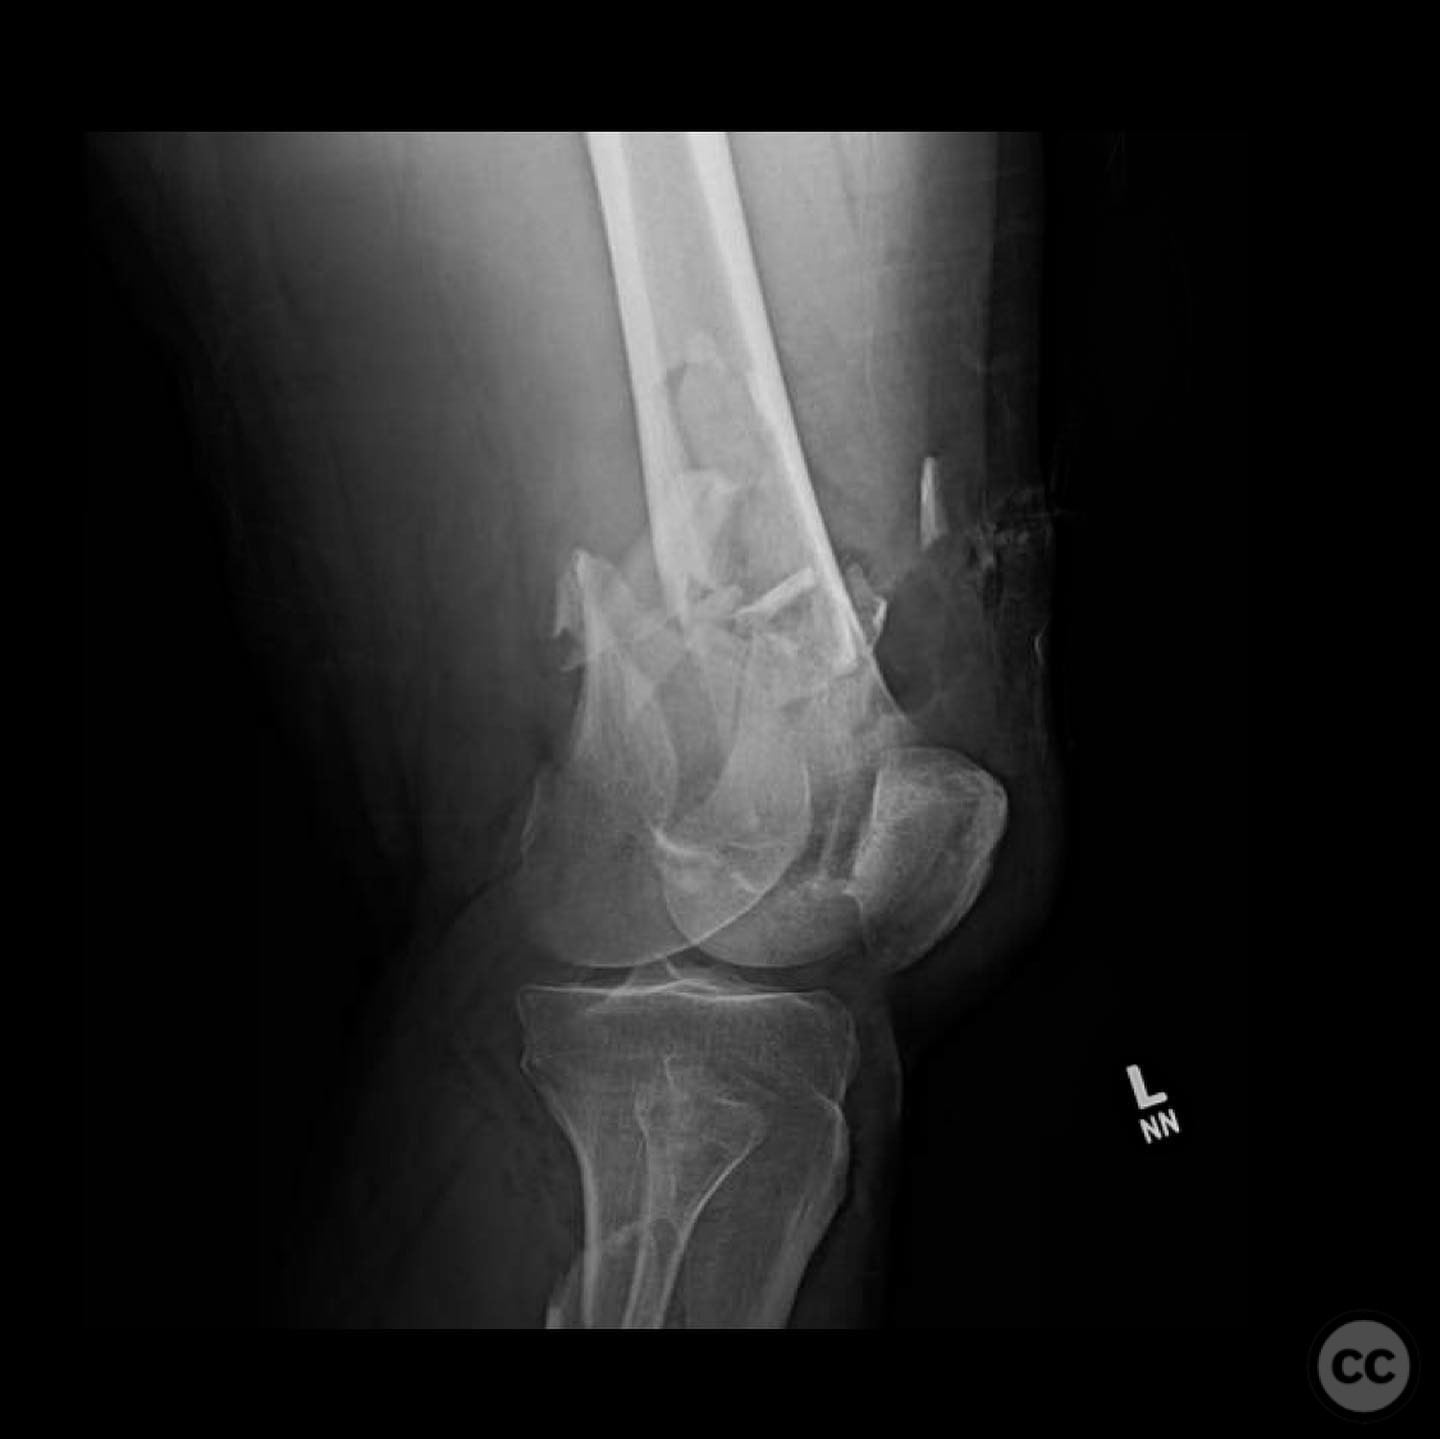

Clinical and radiological findings:  A 44-year-old male cyclist was involved in a collision with a car, resulting in open fractures of the distal femur and segmental tibia. The femoral fracture presented with a 4 cm transverse wound on the anterior aspect, while the tibial fracture had a 2 cm anterolateral wound at the distal site. There were no associated head, chest, or abdominal injuries, and compartment syndrome was not present. Vascular examination was unremarkable.

Planning remarks:  The preoperative plan involved initial debridement and irrigation of both open fractures. The tibia was prioritized for intramedullary nailing, followed by spanning external fixation of the distal femur. Definitive fixation of the distal femur was planned for two days post-initial stabilization.